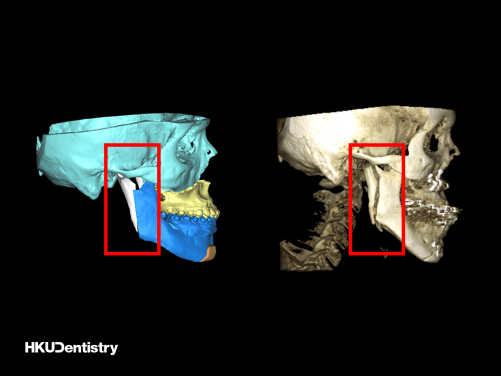

Intraoral vertical ramus osteotomy (IVRO): (Left) The pre-operative virtual surgical planning (red frame); (Right) The post-operative CT scan (red frame).

Mandibular prognathism is a common facial deformity in Hong Kong and Southern China when compared to Western countries. The correction of mandibular prognathism requires orthognathic surgery, which involves creating a split in the jawbone(s) and fix in a planned position. Intraoral vertical ramus osteotomy (IVRO) and sagittal split ramus osteotomy (SSRO) are the two common surgical techniques of the lower jaw to setback the elongated lower jaw. IVRO is an older technique that requires intermaxillary fixation to achieve bone fixation, i.e. locking the upper and lower jaws with wire, for 6 weeks. During this period, the patient can only take fluid diets. SSRO, in contrast, allows internal fixation using titanium plates and screws, which enables immediate jaw function after the surgery. Both techniques are commonly used in Hong Kong and Eastern Asia in treating patients with mandibular prognathism.